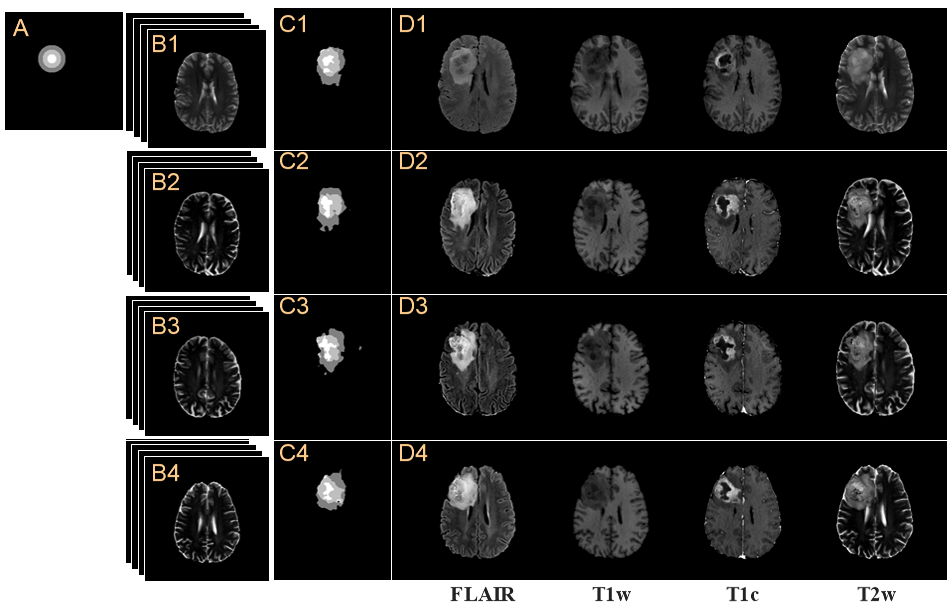

Refer to caption

Figure 4: Data preprocessing for training of the proposed method. (A1) Multi-contrast brain tumor MR images, XTsubscriptX𝑇\textbf{X}_{T}, and (A2) grade tumor mask, mgradesubscript𝑚𝑔𝑟𝑎𝑑𝑒m_{grade} from BraTS 2018. (B) Concentric circles, c1,c2,subscript𝑐1subscript𝑐2c_{1},c_{2}, and c3subscript𝑐3c_{3}, simplified from mgradesubscript𝑚𝑔𝑟𝑎𝑑𝑒m_{grade}. (C1) Shape of the brain and (C2) binary tumor mask, mbinarysubscript𝑚𝑏𝑖𝑛𝑎𝑟𝑦m_{binary} are produced by binarization operator, β()𝛽\beta(\cdot). (D) Multi-contrast brain images are masked in the tumor-parts of XTsubscriptX𝑇\textbf{X}_{T}.

BraTS 2018 [1] is used as the dataset for training of the proposed network. For inputs and ground truths of each network, the given images from the dataset are preprocessed as shown in Fig.4. There are brain tumor MR images, XT,subscriptX𝑇\textbf{X}_{T}, and grade tumor mask, mgrade,subscript𝑚𝑔𝑟𝑎𝑑𝑒m_{grade}, as shown in Fig.4(A1-A2). The concentric circles, c1,c2,subscript𝑐1subscript𝑐2c_{1},c_{2}, and c3,subscript𝑐3c_{3}, by simplifying the tumor mask are shown in Fig.4(B). The shapes of the brain and mbinarysubscript𝑚𝑏𝑖𝑛𝑎𝑟𝑦m_{binary} are shown in Fig.4(C1-C2). Masked brain tumor images are produced by multiplication of a factor of (1mbinary)1subscript𝑚𝑏𝑖𝑛𝑎𝑟𝑦(1-m_{binary}) as shown in Fig.4(D). The proposed networks are trained by using preprocessed images and given images from the dataset, as input and ground truths for each network, such as mbinarysubscript𝑚𝑏𝑖𝑛𝑎𝑟𝑦m_{binary} and mgradesubscript𝑚𝑔𝑟𝑎𝑑𝑒m_{grade}, not m^binarysubscript^𝑚𝑏𝑖𝑛𝑎𝑟𝑦\hat{m}_{binary} and m^gradesubscript^𝑚𝑔𝑟𝑎𝑑𝑒\hat{m}_{grade}. Details of the loss function used in each training will be explained.